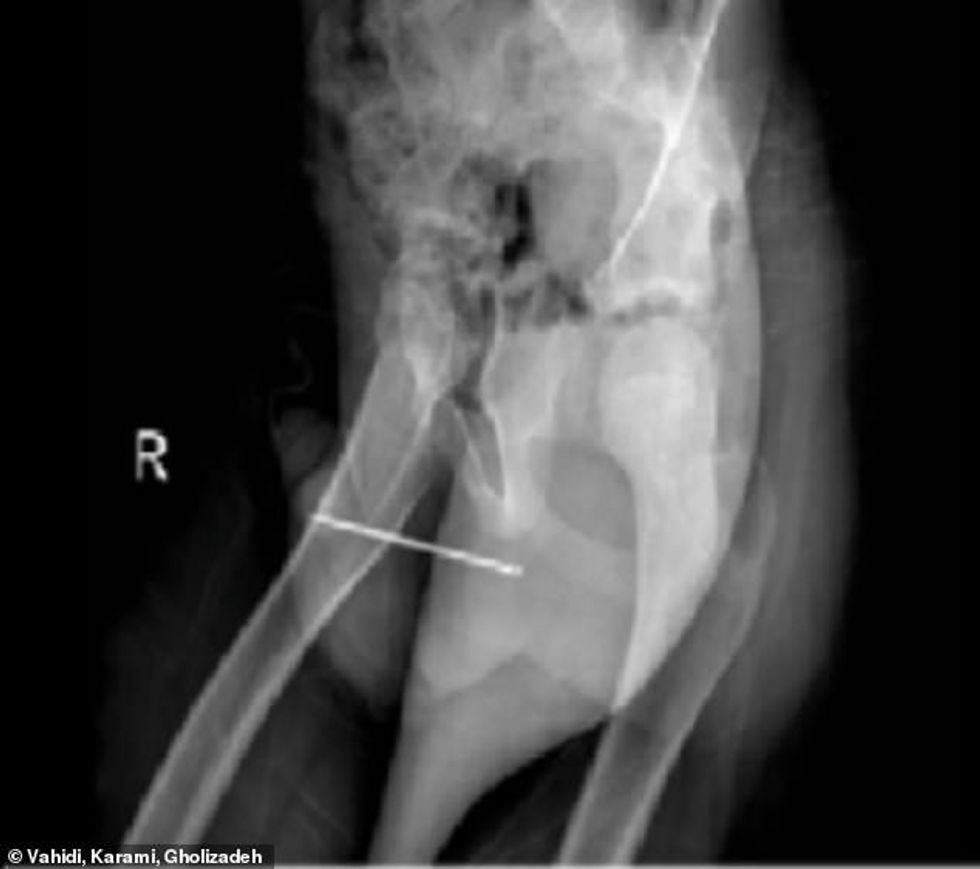

Pas skenimit, doktorët u tronditën kur panë se një gjilpërë 8 centimetërshe ishte futur në penisin e tij dhe pastaj kishte shkuar deri në tubin e tij të fshikëzës, shkruan Daily Mail.

Kur penisi i tij u lëndua, ai kërkoi ndihmë, por nuk e pranoi atë që kishte bërë - ai u dërgua me urgjencë në operacion ku gjilpëra u hoq përmes një operacioni joinvaziv duke përdorur një endoskop që e gjeti gjilpërën.